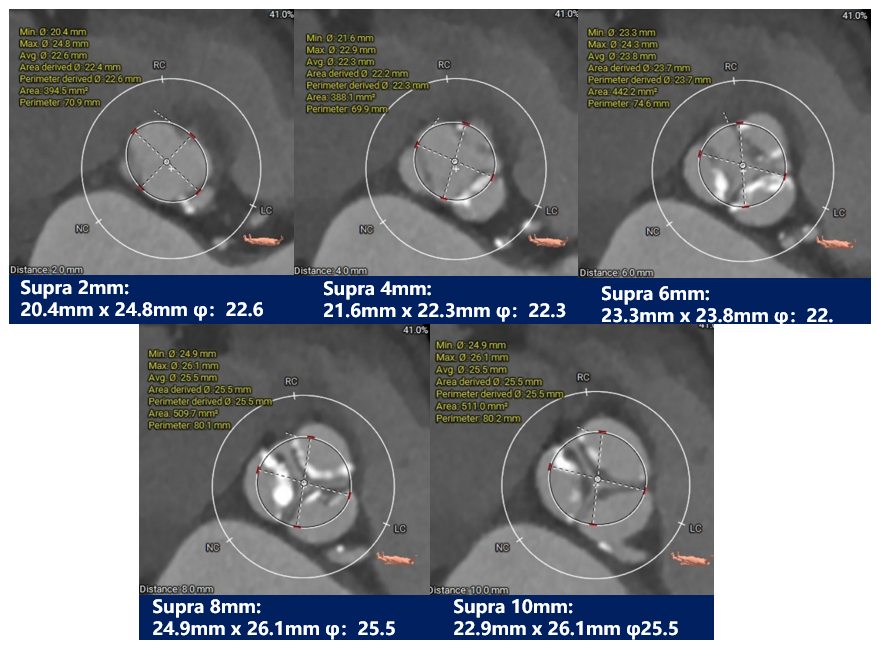

瓣环上解剖结构评估:

瓣上测量: